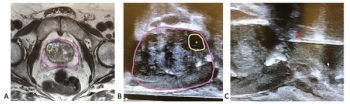

Advanced imaging and improvements in biopsy techniques usher in a new paradigm for screening and diagnosis.